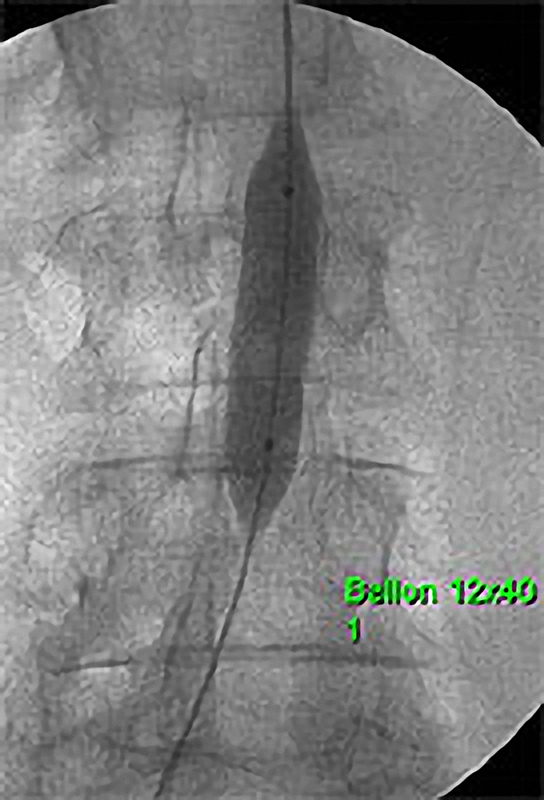

Die PTA (Perkutane Transluminale Angioplastie) im Beckenbereich ist ein minimalinvasives Verfahren zur Behandlung von verengten Beckenarterien. Dabei wird ein dünner Katheter mit einem Ballon über die Leiste in die verengte Arterie eingeführt. Der Ballon wird an der Engstelle entfaltet und dehnt die Arterie auf, um den Blutfluss zu verbessern. Oft wird zusätzlich ein Stent eingesetzt, um die Arterie dauerhaft offen zu halten. Die PTA wird meist in örtlicher Betäubung durchgeführt und ermöglicht eine schnelle Erholung. Sie ist eine bewährte Alternative zur offenen Operation bei Durchblutungsstörungen im Becken- und Beinbereich.